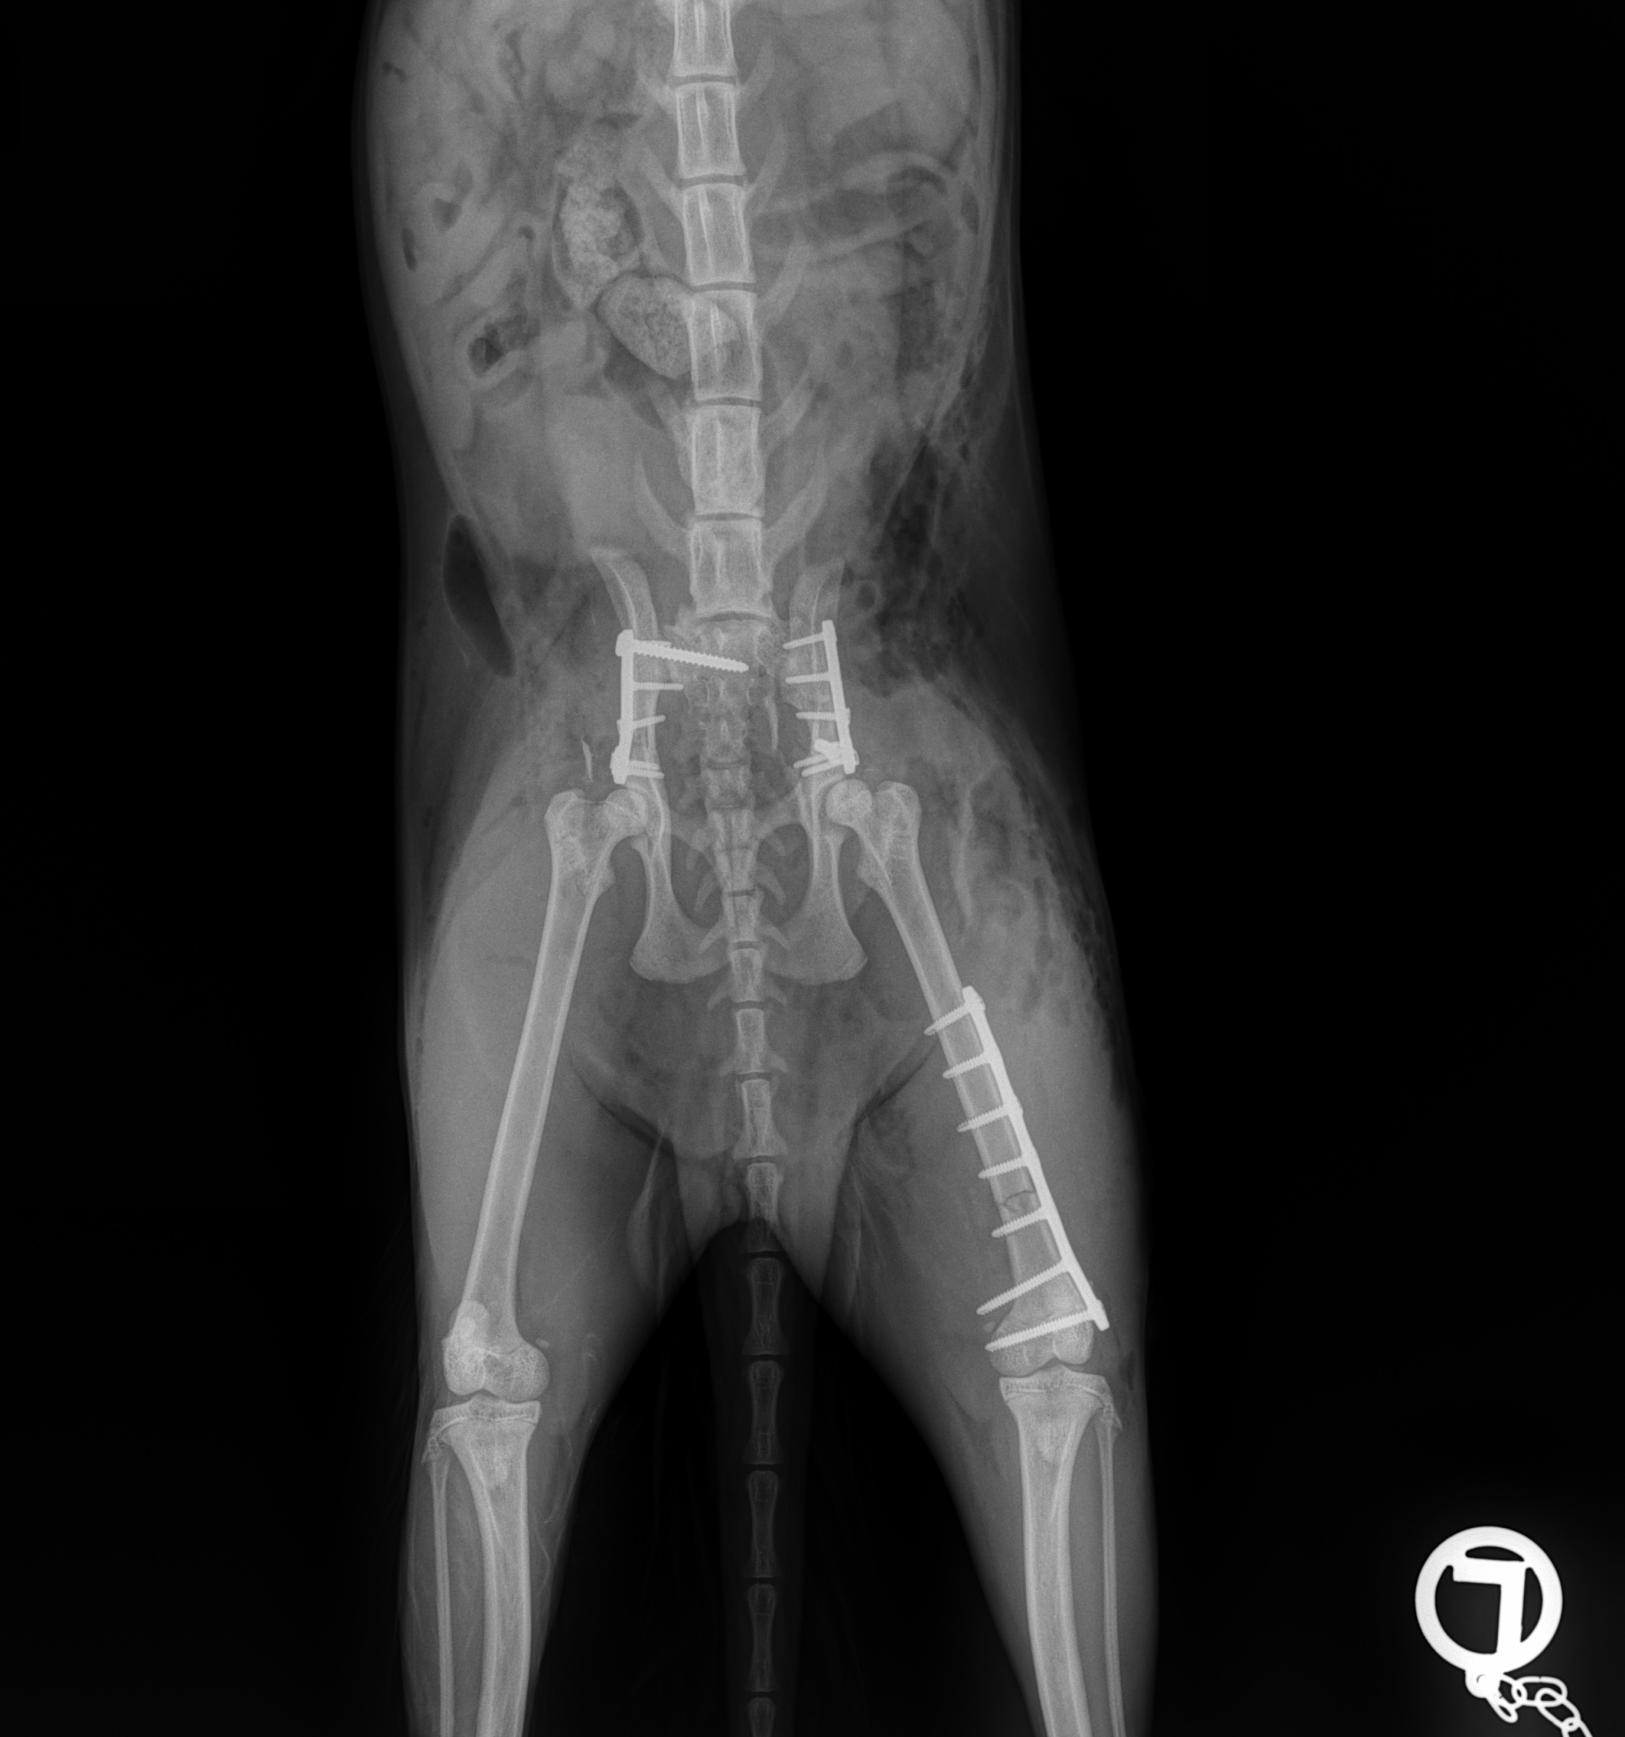

Case Overview In November 2025, Skeeter, a 14-week-old Doodle puppy weighing ...